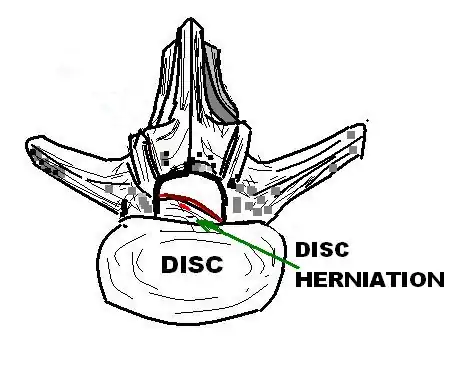

[1] A disc protrusion is a medical condition that can occur in some vertebrates, including humans, in which the outermost layers of the anulus fibrosus of the intervertebral discs of the spine are intact but bulge when one or more of the discs are under pressure.

Many disk abnormalities seen on MRI that are loosely referred to as "herniation" are actually just incidental findings. These may be unrelated to any symptoms and are just bulges of the anulus fibrosus. Jensen and colleagues, in an MRI study of the lumbar spine in 98 asymptomatic adults, found that in more than half, there was a symmetrical extension of a disc (or discs) beyond the margins of the interspace (bulging). In 27 percent, there was a focal or asymmetrical extension of the disc beyond the margin of the interspace (protrusion), and in only 1 percent was there more extreme extension of the disc (extrusion or sequestration). These findings emphasize the importance of using precise terms in describing the imaging abnormalities and evaluating them strictly in the context of the patient's symptoms.[1]

A disc protrusion may progress to a spinal disc herniation, a condition in which there is a tear in the anulus fibrosus.[2] The most common area to have a disc protrusion is in the Lumbar Spine, specifically L-5.[2]